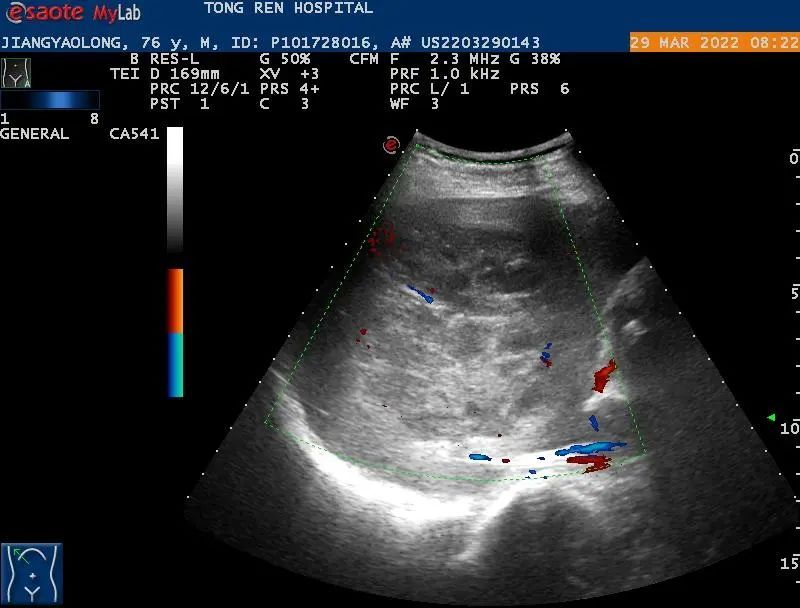

术前对病灶进行充分评估,并做了超声造影,肝脓肿较成人拳头略大,內见较多的分隔。

于是,我们决定进行肝脓肿的置管引流。同时,患者的核酸报告结果也为阴性,在封控的情况下,我们第一次在身穿防护服及三层手套的条件下进行手术,抽出脓液20ml,并顺利完成了置管引流,过程顺利,病人安全。

此项技术是指通过超声评估,确定患者是否满足肝脓肿穿刺的条件、有无进针的安全路径以规避肝内重要管道结构(如肝动脉、肝静脉、肝内胆管及门静脉等)。患者通常局部麻醉,在超声实时监测下,医生可从入皮肤开始,全程直观的观察并操作穿刺针以最安全的路径到达肝脓肿部位,抽吸脓液并置管引流,具有安全、创伤小等优点。